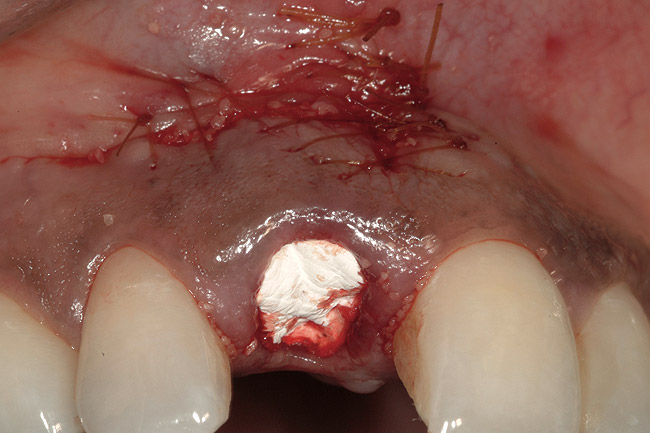

Figure 11  Extraction site following grafting, flap suturing, and adaptation and fixation of resorbable collagen membrane.

Figure 11

In the present case, a submarginal incision was made at the mucogingival gingival junction, revealing the facial fenestration defect (Figure 10 ). The mucosa was elevated to access and graft both the socket and fenestration defect. Both sites were protected by a collagen membrane (Bio-Gide®), and sutured to close the submarginal incision (Figure 11 ). Medical cyanoacrylate was placed over the socket wound to stabilize the collagen membrane. Healing was uneventful, and the soft-tissue contours suggested preservation of the alveolar contours at the time of extraction. Five months after extraction and augmentation, the findings from a clinical postoperative radiograph demonstrated evidence of notable graft containment as reflected by the overall radiopacity of the extraction site, even coronal to the socket. The site was reentered for implant placement. Flap elevation revealed the dense bone ridge with complete incorporation of the particulate graft material. The osteotomy for implant placement was prepared with a trephine bur, and the resulting specimen was submitted for histologic evaluation. The histologic findings revealed evidence of robust osteogenesis throughout the bone core, including the coronal aspect supporting the soft tissue. New bone was found in close amalgamation with the FDBA-graft particles throughout the specimen. A dental implant was placed at the site in a single-stage surgery and allowed to heal for 5 months prior to the restoration. The esthetic outcome was highly acceptable, with preservation of the marginal and papillary gingiva contours (Figure 12 ). The radiographic findings showed consistent normal bone remodeling and implant integration (Figure 13 ).